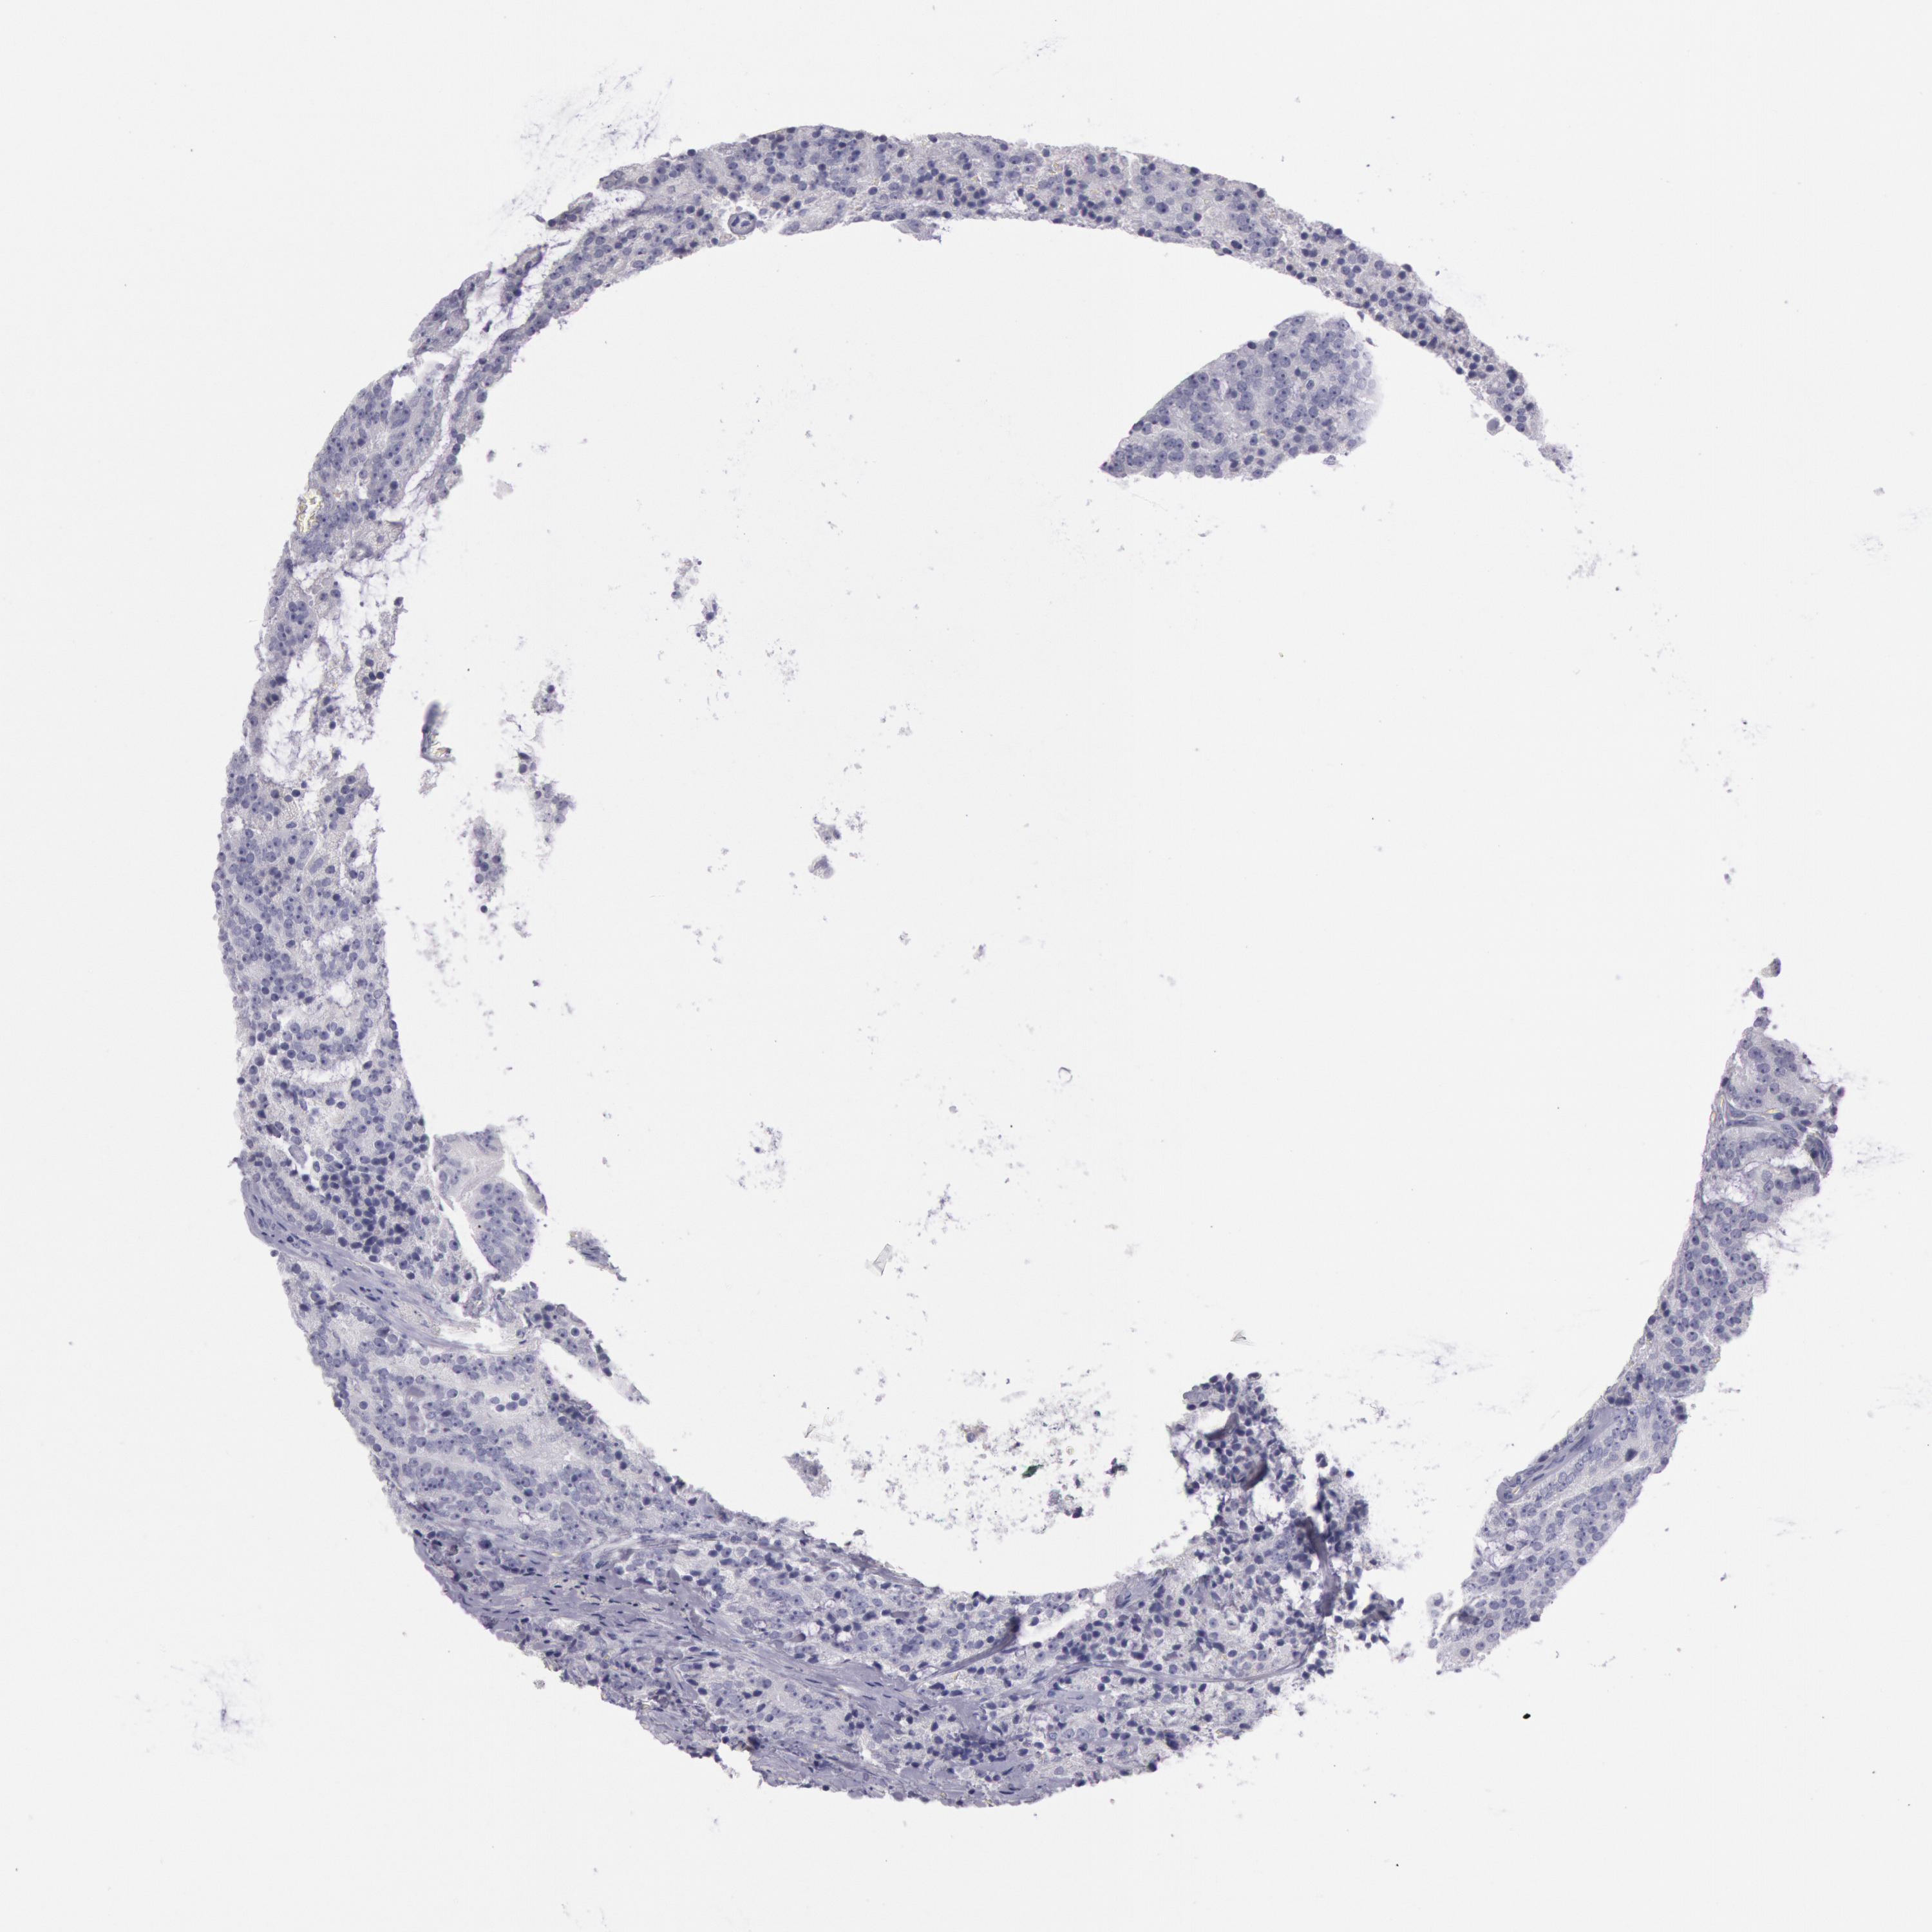

PROSTATE CANCER - Protein expressioni

A mouse-over function shows sample information and annotation data. Click on an image to view it in a full screen mode. Samples can be filtered based on level of antibody staining by selecting one or several of the following categories: high, medium, low and not detected. The assay and annotation is described here.

Note that samples used for immunohistochemistry by the Human Protein Atlas do not correspond to samples in the TCGA dataset.

Antibody stainingi

Antibody staining in the annotated cell types in the current human tissue is reported as not detected, low, medium, or high, based on conventional immunohistochemistry profiling in selected tissues. This score is based on the combination of the staining intensity and fraction of stained cells.

Each image is clickable and will lead to virtual microscopy that enables deeper exploration of all samples and also displays staining intensity scores, fraction scores and subcellular localization as well as patient and tissue information for each sample.

Adenocarcinoma, Medium grade

Adenocarcinoma, Low grade

Adenocarcinoma, High grade

Adenocarcinoma, NOS